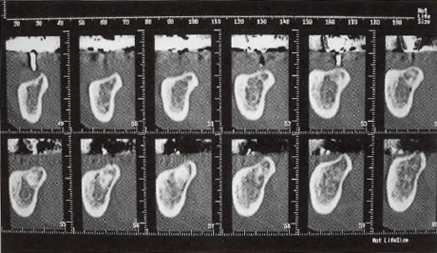

- (1)デンタルⅩ線・パノラマⅩ線撮影

- (2)必要ならば撮影用ステントを用いてCT撮影を行います。

画像診断ソフト(シンプラント; SIM/Plant)などを用いる場合もあります。